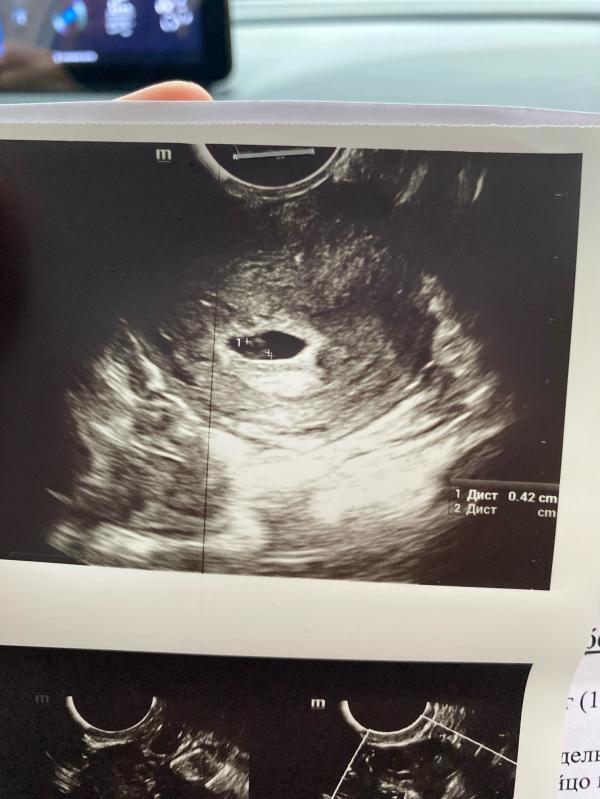

Плодное яйцо 12.3мм

Желточный мешок 4мм , эмбриончика нету 🥲